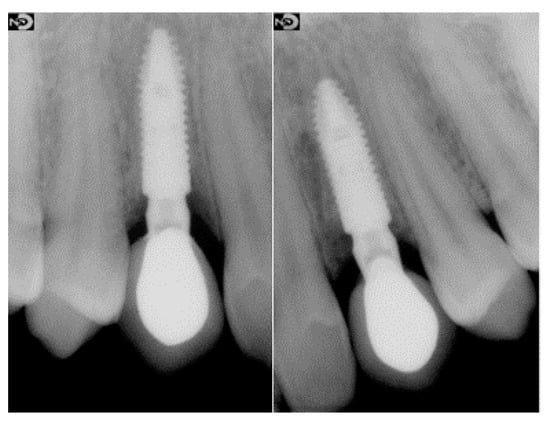

2.3. Surgical and Prosthetic Workflow

2.4. Outcome